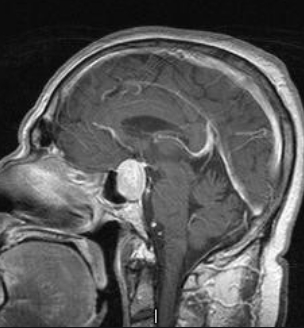

18岁花季少女突发闭经,脑内竟藏巨大危机! 起初,米拉只是月经迟迟不来,本以为只是内分泌失调,谁知医生却建议她前往神经外科检查。核磁共振结果令...